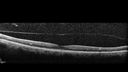

PDR and DME and VH338 views57 year old diabetic man with vision loss in the left eye for several months. He has DME in the left eye and VH in the left eye and PDR in both eyes. He has been started in the left eye on Anti-VEGF therapy. VA on presentation was 20/25 OD and 20/200 OSDec 30, 2019

PDR and DME and VH403 views57 year old diabetic man with vision loss in the left eye for several months. He has DME in the left eye and VH in the left eye and PDR in both eyes. He has been started in the left eye on Anti-VEGF therapy. VA on presentation was 20/25 OD and 20/200 OSDec 30, 2019

PDR and DME and VH331 views57 year old diabetic man with vision loss in the left eye for several months. He has DME in the left eye and VH in the left eye and PDR in both eyes. He has been started in the left eye on Anti-VEGF therapy. VA on presentation was 20/25 OD and 20/200 OSDec 30, 2019

PDR and DME and VH318 views57 year old diabetic man with vision loss in the left eye for several months. He has DME in the left eye and VH in the left eye and PDR in both eyes. He has been started in the left eye on Anti-VEGF therapy. VA on presentation was 20/25 OD and 20/200 OSDec 30, 2019

PDR and DME and VH419 views57 year old diabetic man with vision loss in the left eye for several months. He has DME in the left eye and VH in the left eye and PDR in both eyes. He has been started in the left eye on Anti-VEGF therapy. VA on presentation was 20/25 OD and 20/200 OSDec 30, 2019

PDR and DME and VH411 views57 year old diabetic man with vision loss in the left eye for several months. He has DME in the left eye and VH in the left eye and PDR in both eyes. He has been started in the left eye on Anti-VEGF therapy. VA on presentation was 20/25 OD and 20/200 OSDec 30, 2019

PDR and DME and VH341 views57 year old diabetic man with vision loss in the left eye for several months. He has DME in the left eye and VH in the left eye and PDR in both eyes. He has been started in the left eye on Anti-VEGF therapy. VA on presentation was 20/25 OD and 20/200 OSDec 30, 2019

PDR and DME and VH340 views57 year old diabetic man with vision loss in the left eye for several months. He has DME in the left eye and VH in the left eye and PDR in both eyes. He has been started in the left eye on Anti-VEGF therapy. VA on presentation was 20/25 OD and 20/200 OSDec 30, 2019

PDR and DME and VH413 views57 year old diabetic man with vision loss in the left eye for several months. He has DME in the left eye and VH in the left eye and PDR in both eyes. He has been started in the left eye on Anti-VEGF therapy. VA on presentation was 20/25 OD and 20/200 OSDec 30, 2019

PDR and DME and VH362 views57 year old diabetic man with vision loss in the left eye for several months. He has DME in the left eye and VH in the left eye and PDR in both eyes. He has been started in the left eye on Anti-VEGF therapy. VA on presentation was 20/25 OD and 20/200 OSDec 30, 2019

PDR and DME and VH379 views57 year old diabetic man with vision loss in the left eye for several months. He has DME in the left eye and VH in the left eye and PDR in both eyes. He has been started in the left eye on Anti-VEGF therapy. VA on presentation was 20/25 OD and 20/200 OSDec 30, 2019

PDR and DME and VH424 views57 year old diabetic man with vision loss in the left eye for several months. He has DME in the left eye and VH in the left eye and PDR in both eyes. He has been started in the left eye on Anti-VEGF therapy. VA on presentation was 20/25 OD and 20/200 OSDec 30, 2019

PDR and DME and VH383 views57 year old diabetic man with vision loss in the left eye for several months. He has DME in the left eye and VH in the left eye and PDR in both eyes. He has been started in the left eye on Anti-VEGF therapy. VA on presentation was 20/25 OD and 20/200 OSDec 30, 2019

PDR and DME and VH321 views57 year old diabetic man with vision loss in the left eye for several months. He has DME in the left eye and VH in the left eye and PDR in both eyes. He has been started in the left eye on Anti-VEGF therapy. VA on presentation was 20/25 OD and 20/200 OSDec 30, 2019

PDR and DME and VH355 views57 year old diabetic man with vision loss in the left eye for several months. He has DME in the left eye and VH in the left eye and PDR in both eyes. He has been started in the left eye on Anti-VEGF therapy. VA on presentation was 20/25 OD and 20/200 OSDec 30, 2019

PDR and DME and VH396 views57 year old diabetic man with vision loss in the left eye for several months. He has DME in the left eye and VH in the left eye and PDR in both eyes. He has been started in the left eye on Anti-VEGF therapy. VA on presentation was 20/25 OD and 20/200 OSDec 30, 2019

PDR and DME and VH389 views57 year old diabetic man with vision loss in the left eye for several months. He has DME in the left eye and VH in the left eye and PDR in both eyes. He has been started in the left eye on Anti-VEGF therapy. VA on presentation was 20/25 OD and 20/200 OSDec 30, 2019

PDR and DME and VH350 views57 year old diabetic man with vision loss in the left eye for several months. He has DME in the left eye and VH in the left eye and PDR in both eyes. He has been started in the left eye on Anti-VEGF therapy. VA on presentation was 20/25 OD and 20/200 OSDec 30, 2019

PDR and DME and VH418 views57 year old diabetic man with vision loss in the left eye for several months. He has DME in the left eye and VH in the left eye and PDR in both eyes. He has been started in the left eye on Anti-VEGF therapy. VA on presentation was 20/25 OD and 20/200 OSDec 30, 2019

PDR and DME and VH371 views57 year old diabetic man with vision loss in the left eye for several months. He has DME in the left eye and VH in the left eye and PDR in both eyes. He has been started in the left eye on Anti-VEGF therapy. VA on presentation was 20/25 OD and 20/200 OSDec 30, 2019

PDR and DME and VH328 views57 year old diabetic man with vision loss in the left eye for several months. He has DME in the left eye and VH in the left eye and PDR in both eyes. He has been started in the left eye on Anti-VEGF therapy. VA on presentation was 20/25 OD and 20/200 OSDec 30, 2019

PDR and DME and VH364 views57 year old diabetic man with vision loss in the left eye for several months. He has DME in the left eye and VH in the left eye and PDR in both eyes. He has been started in the left eye on Anti-VEGF therapy. VA on presentation was 20/25 OD and 20/200 OSDec 30, 2019

PDR and DME and VH346 views57 year old diabetic man with vision loss in the left eye for several months. He has DME in the left eye and VH in the left eye and PDR in both eyes. He has been started in the left eye on Anti-VEGF therapy. VA on presentation was 20/25 OD and 20/200 OSDec 30, 2019

PDR and DME and VH407 views57 year old diabetic man with vision loss in the left eye for several months. He has DME in the left eye and VH in the left eye and PDR in both eyes. He has been started in the left eye on Anti-VEGF therapy. VA on presentation was 20/25 OD and 20/200 OSDec 30, 2019

PDR and DME and VH441 views57 year old diabetic man with vision loss in the left eye for several months. He has DME in the left eye and VH in the left eye and PDR in both eyes. He has been started in the left eye on Anti-VEGF therapy. VA on presentation was 20/25 OD and 20/200 OSDec 30, 2019